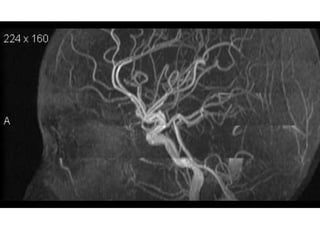

7- MRA demonstrate Right

MCA-

1- Aneurysm

2- AVM

3- Thrombus

4- Hypoplasia